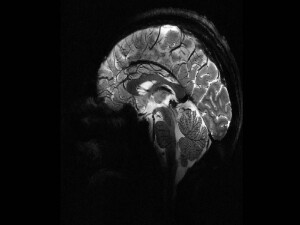

Gazete Duvar'ın haberine göre Korona virüsüyle ilgili sağlıkçılardan edindiği bilgileri de derleyerek uyarılarda bulunan Dr. Atilla Özmumcu, hastalığa ‘Covid-19 Bağlantılı Çoklu Sistem Sendormu’ adı verilmesi gerektiğini ifade etti. Diş hekimi Özmumcu, her yaştan hastada deliryum (bilinçte bulanıklık, kendini birşeylere odaklamada sorun yaşama, garip hayaller görme, etraftaki eşyaların şekil ya da yer değiştirdiğini görme ya da anlamsız öfkelenme) oluştuğunu belirtti.

Çok şiddetli hipoksi yapıyor. Neredeyse tüm yoğun bakım doktor ve hemşirelerinden bunu öğrendiğimi özellikle vurgulamak isterim. Hastalarda yaş gözetmeksizin delirium benzeri bir tablo oluşuyor. Tablo hastalık şiddetlendikçe derinleşiyor. Hastaların bir anda agresifleşerek kateterlerini çıkarmaya çalıştıklarını, nerede olduklarını hatırlamadıklarını, kendisiyle 10 dakika önce ilgilenen hemşireyi tanımayıp hatırlamayan, yataktan kalkıp eve gitmek isteyen hastalar var. Bir kısmına sedasyon vermek zorunda kalmışlar. Bir kısmını yasal temsilcisinden izin alarak el ve ayak bileklerinden yatağa bağlamışlar.